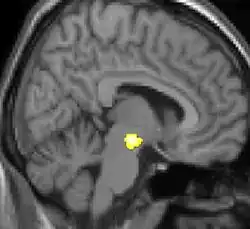

One of the first VBM studies and one that came to attention in mainstream media was a study on the hippocampus brain structure of London taxicab drivers.[7] The VBM analysis showed the back part of the posterior hippocampus was on average larger in the taxi drivers compared to control subjects while the anterior hippocampus was smaller. London taxi drivers need good spatial navigational skills and scientists have usually associated hippocampus with this particular skill.